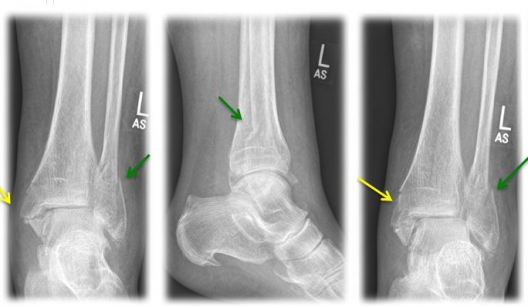

A combined fracture of the inner and outer ankle is referred to as a "bimalleolar ankle fracture" (see Fig. 3). If, in addition, the posterior lower tibia edge (=Volkmann's triangle) is broken, it is called "trimalleolar ankle fracture".

Fig. 3) "Bimalleolar ankle joint fracture" left x-rayed in 3 planes (a.p., lateral, internal rotation) with an internal ankle fracture (yellow arrow) and a spiral external ankle fracture (green arrow)